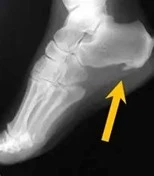

اندازه این زائده استخوانی میتواند به ۲ سانتیمتر برسد، اما لزوما همیشه با چشم غیرمسلح دیده نمیشود. بیشتر از طریق تستهای تصویربرداری یا آزمایشهایی که برای تشخیص سایر مشکلات پا انجام میشوند، قابل تشخیص است.